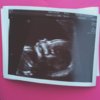

Så fint bilde! Sutter på tommelenVis vedlegget 167309

Så fint bilde! Sutter på tommelen![]()